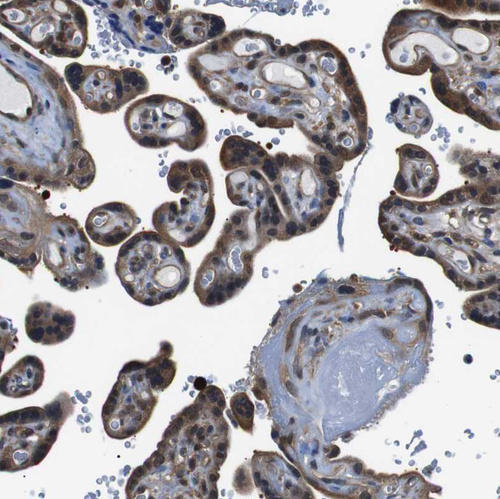

Immunohistochemical staining of human testis shows strong cytoplasmic positivity in cells in seminiferous ducts.